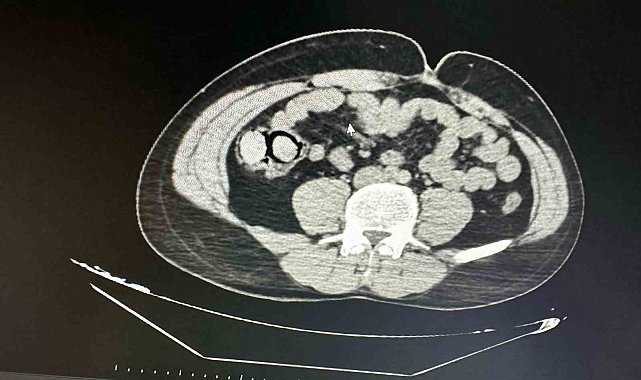

Bingöl'de akıllara durgunluk veren bir olay gerçekleşti. Otobüs yolculuğu sırasında polis ekiplerince durdurulan yabancı uyruklu iki şahsın midesinden 10 parça halinde 113 gram metamfetamin çıktı.

Bingöl Emniyet Müdürlüğü Narkotik Suçlarla Mücadele Şube Müdürlüğüne bağlı narko-timleri akıllara durgunluk veren bir uyuşturucu kaçakçılığını çözdü. Ekiplerin çalışmaları neticesinde otobüs ile Bingöl'e gelen şüpheli yabancı uyruklu 2 şahsın iç beden muayenesinde 10 parça halinde 113 gram metamfetamin maddesi tespit edildi. Emniyetteki işlemlerinin ardından mahkemeye çıkarılan 2 şahıs, uyuşturucu madde ticareti yapmak suçundan tutuklanarak Elazığ Kapalı ceza infaz kurumuna teslim edildi.